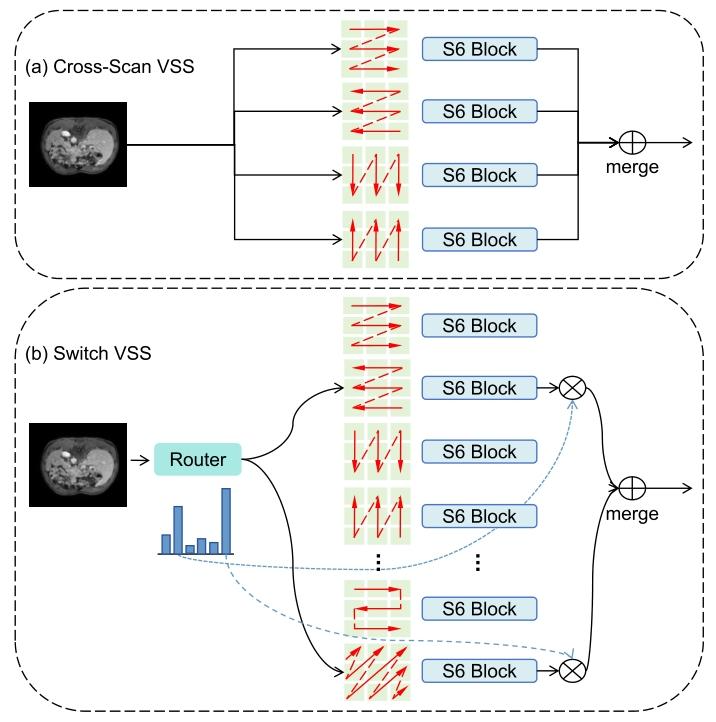

Fig. 1. (a) Cross-Scan VSS: Each sample undergoes processing via four predefined scanning strategies, followed by engagement with the respective S6Block. (b) Proposed Switch VSS: The Mixture-of-Scans (MoS) mechanismautomatically identifies the appropriate scan head for each sample, followedby output fusion through a weighted summation.

图1 (a)交叉扫描视觉状态空间(Cross-Scan VSS):每个样本通过四种预定义的扫描策略进行处理,随后进入对应的S6Block模块。 (b)所提切换视觉状态空间(Switch VSS):混合扫描(MoS)机制自动为每个样本确定适配的扫描头,之后通过加权求和对输出结果进行融合。